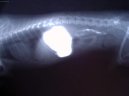

| Léčba interních onemocnění (Veterinární zákroky) - V mnoha případech je nezbytné dlouhodobé podávání antibiotik k zabránění růstu patologické bakteriální mikroflóry ve střevech a aplikace vitamínů. |